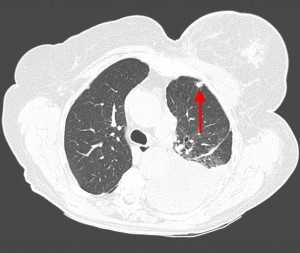

КТ: метастазы в легких при раке молочной железы. На изображении справа красной звездочкой отмечен опухолевый узел в молочной железе, красными стрелками - область прорастания опухоли в грудную стенку. Синими звездочками отмечен карциноматозный плеврит — скопление жидкости в плевральной полости. Слева стрелкой отмечен вторичный узел.